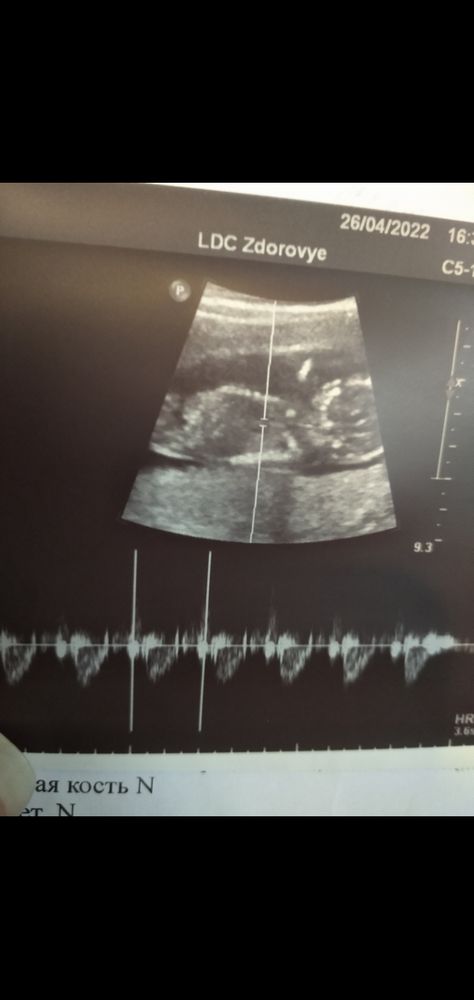

Ну дак вот, сейчас срок 13+3 (по УЗИ оказалось уже 13+6), ну и врач говорит, оооой рано, ооой мы не говорим, смотрю на экран, вроде бугорок, стоит торчком, ну думаю сейчас скажет хоть что-то, ааа нет, померила серцебиение, говорит 170 девочка "наверно" 🤣🤣🤣, а конце УЗИ, оооо 150 похоже пацан🤣🤣🤣да ептить, буду ждать второй скрининг, ещё и фото выдала ни единого бугорочка не видно🙈

Евгения , в другом был фокус..у девок моих сердце как у зайцев стучит хаотично. У парней с опред интервалом.как дробь..бум бум..а у девок бум бум....бум..как-то так если словами

Анна, ого, ну у меня тоже похоже на дробь было, ну в общем узнаю на втором скрининге